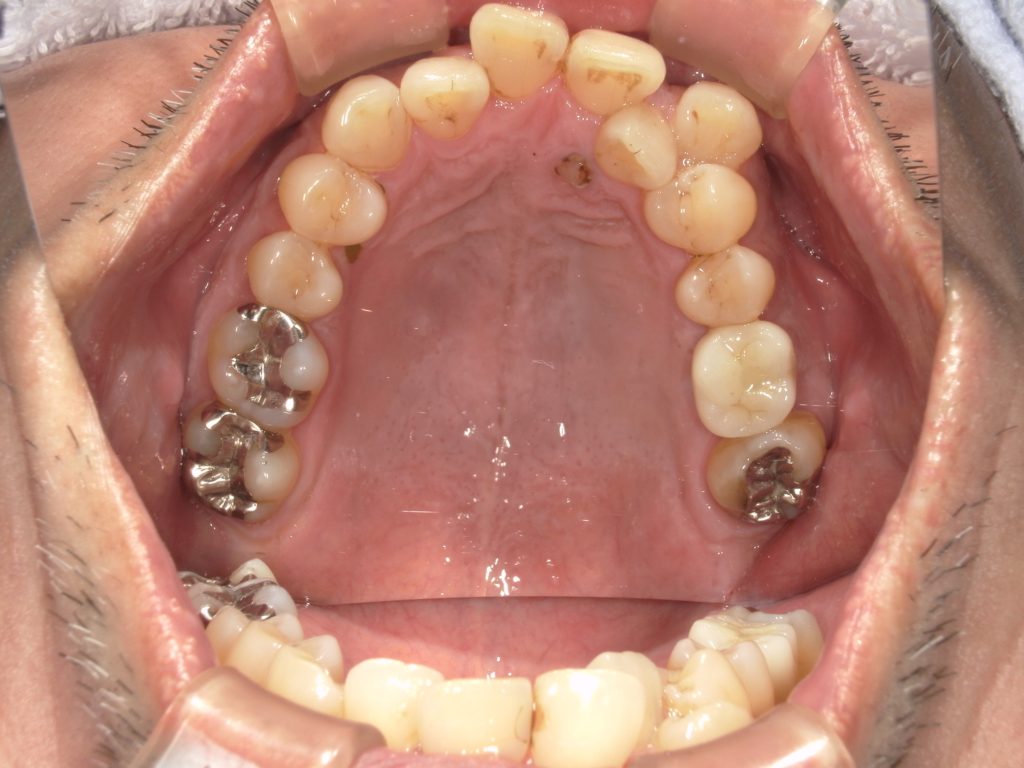

Y様インプラント実例 #44

左の上下の奥歯をインプラントで治療しています。

左下の奥歯は歯を抜くのと同時にインプラントの埋め込みを行っています。

被せものは上下、セラミックスで作っています。

治療前

治療後